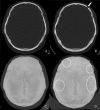

This is a case of a 22-year-old, HIV-negative, male patient with asymptomatic syphilitic osteomyelitis of the skull in the context of secondary syphilis. The diagnosis was made based on serology as well as CT and MRI scans. CT volumetric data was post-processed with cinematic rendering, which is a novel algorithm that allows for a photorealistic visualization of the lesions. Imaging and follow-up scans after treatment confirmed the diagnosis without the need to perform invasive procedures such as a biopsy.